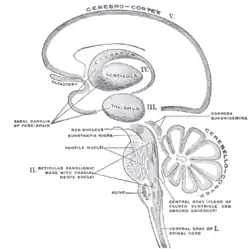

Transverse section through the midbrain showing the location of the red nuclei. The superior colliculi are at the top of image and the cerebral peduncles at the bottom of image – both in section. | |

The red nucleus or nucleus ruber is a structure in the rostral midbrain involved in motor coordination.[1] The red nucleus is pale pink, which is believed to be due to the presence of iron in at least two different forms: hemoglobin and ferritin.[2][3] The structure is located in the tegmentum of the midbrain next to the substantia nigra and comprises caudal magnocellular and rostral parvocellular components.[1] The red nucleus and substantia nigra are subcortical centers of the extrapyramidal motor system.

Transverse section through mid-brain. Transverse section of mid-brain at level of superior colliculi.

Transverse section of mid-brain at level of superior colliculi. Coronal section of brain immediately in front of pons.